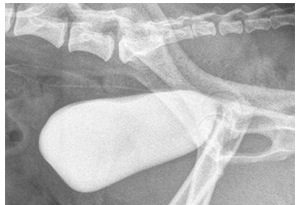

What type of contrast study?

Double contrast cystogram